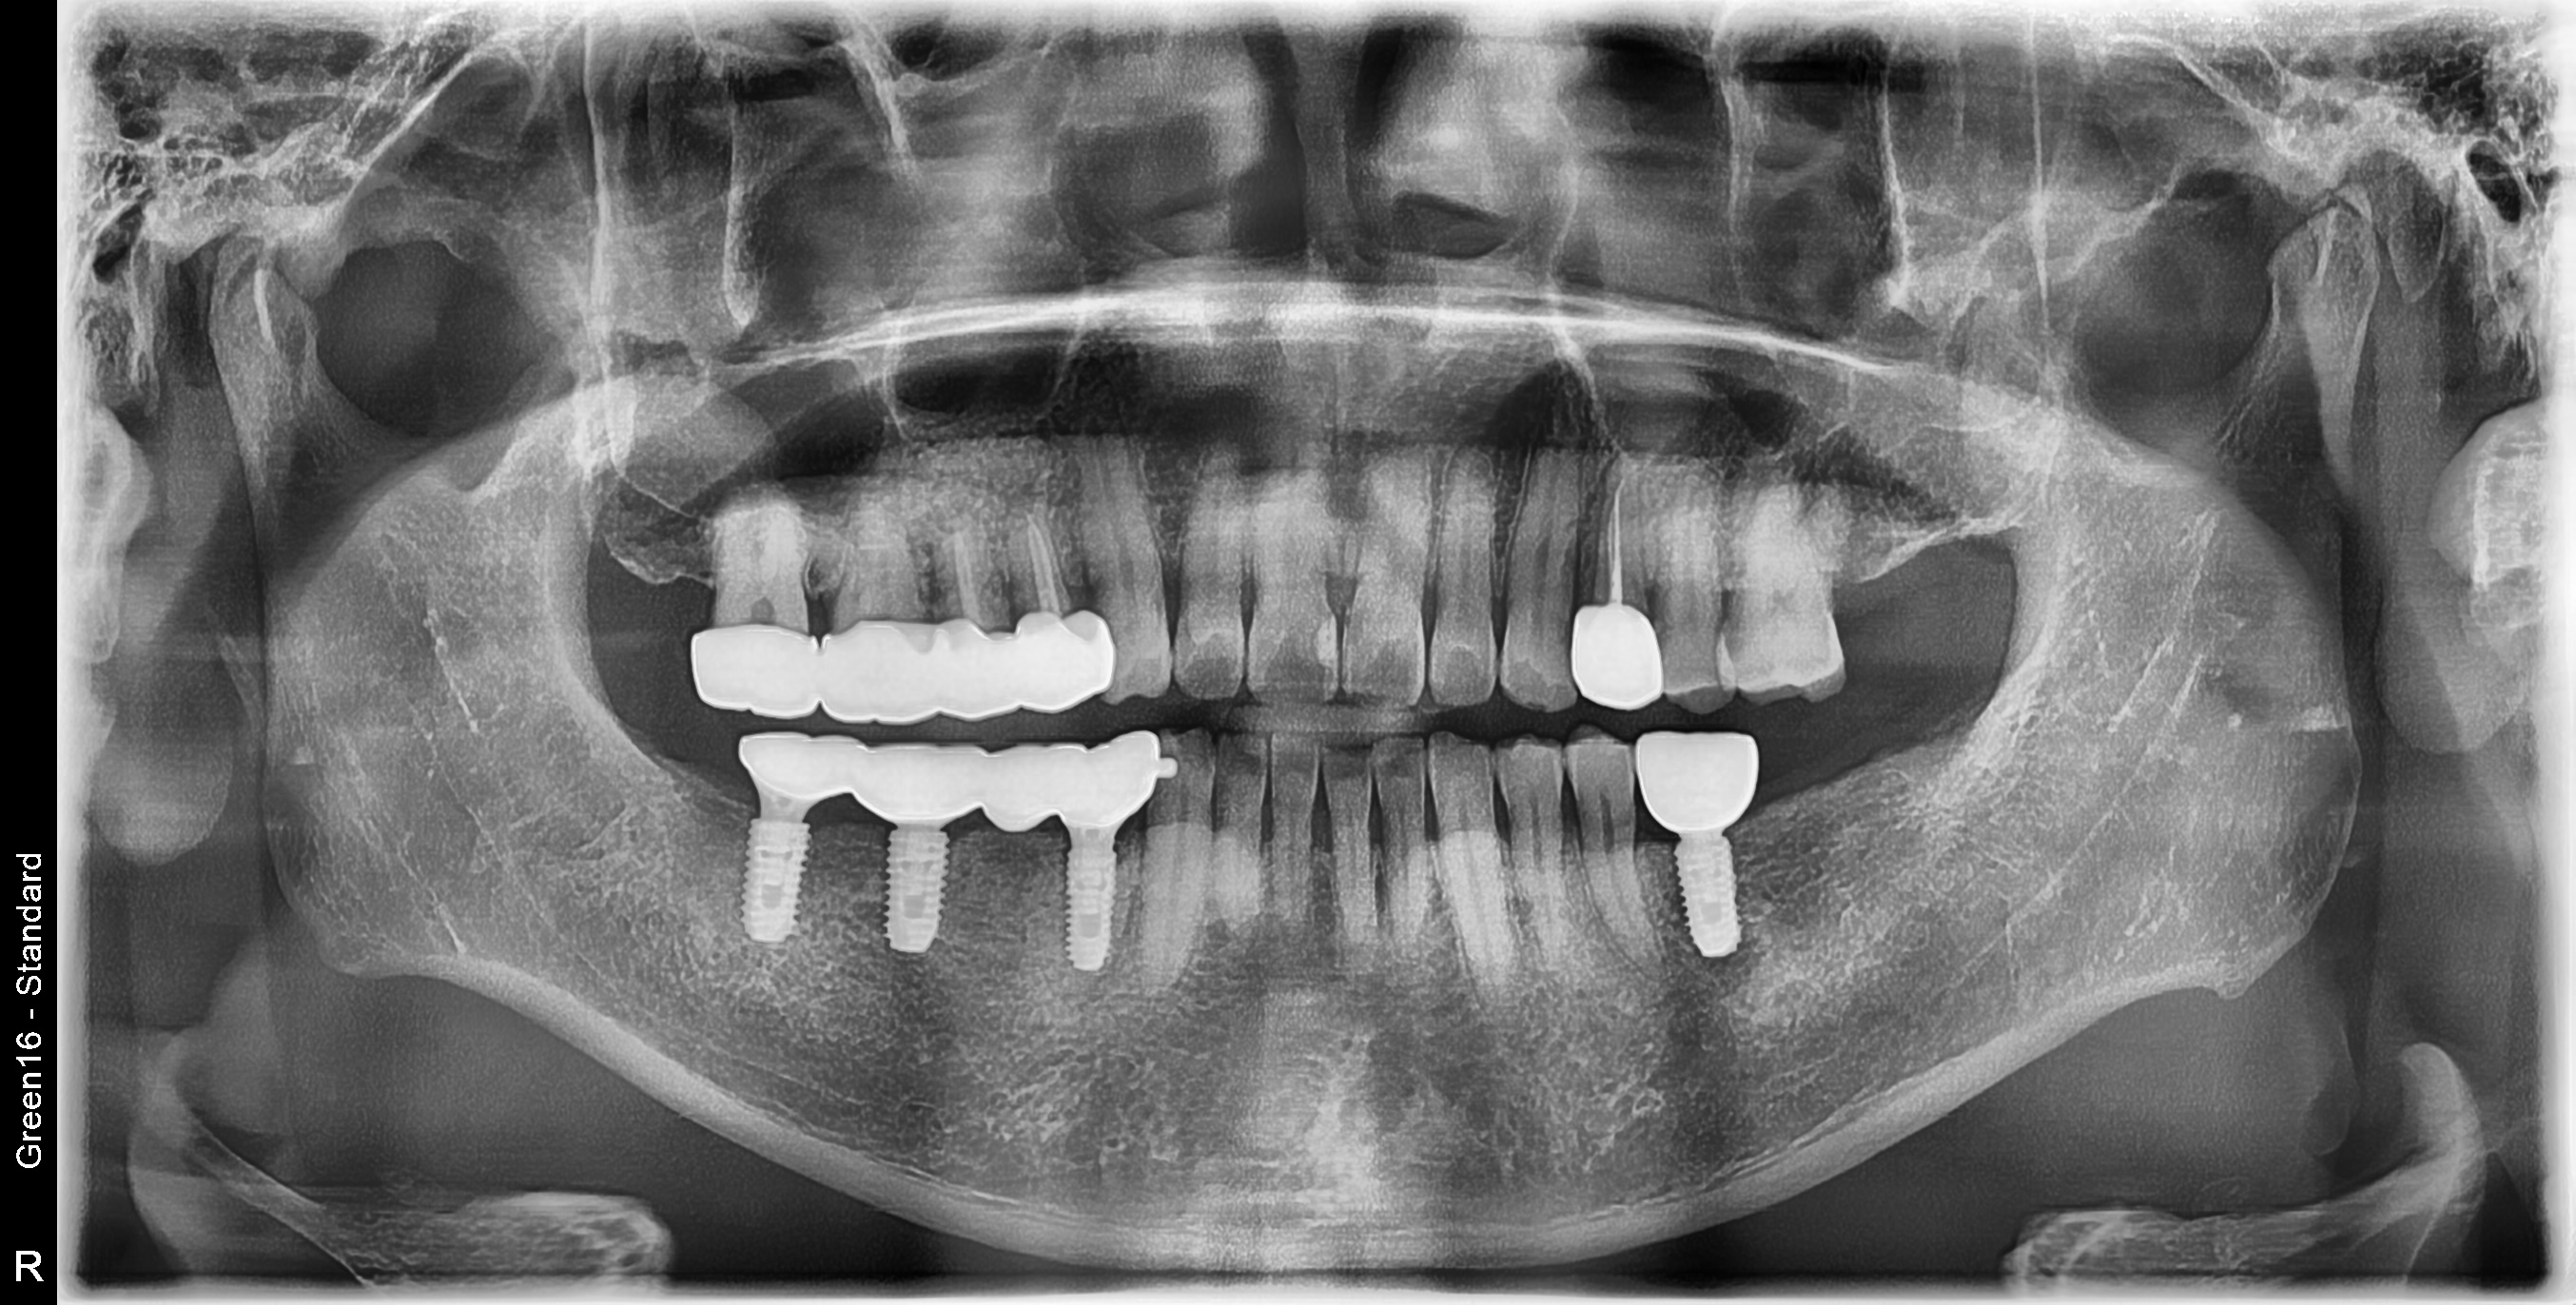

하악 구치부 식립사례

전후사진

상악 구치부 식립사례